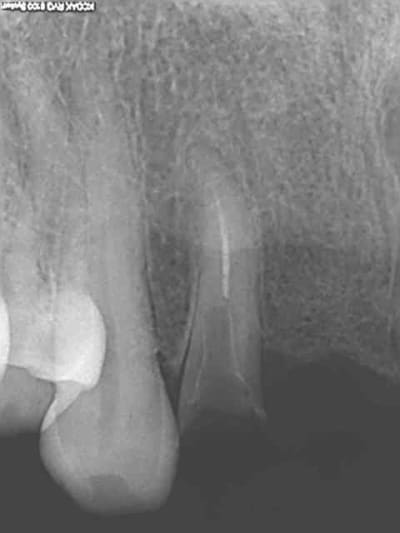

Bridge descellé, re-scellé plusieurs fois par plusieurs dentistes différents. la charte de bonne pratique est respectée (vu qu'on ne fait pas de prothèse) on re-scelle sur de la merde.

Bonjour l'odeur dans les canaux, Il fallait bien qu'il y en ai un qui y mette un terme.

Bien sur l'essentiel porte sur la ventilation des honoraires du bridge à refaire.

Je ne fais jamais de cathétérisme manuel, ca évite de casser des limes 15 de merde dans les canaux. d'ailleurs je ne sais pas ou elle est passée celle là, quelque part dans l'aspi je suppose.))))))

Reprise au R25 puis R40.

Charte de bonne pratique de merde, qui intéresse tout sauf la pratique. Ca m'énerve.